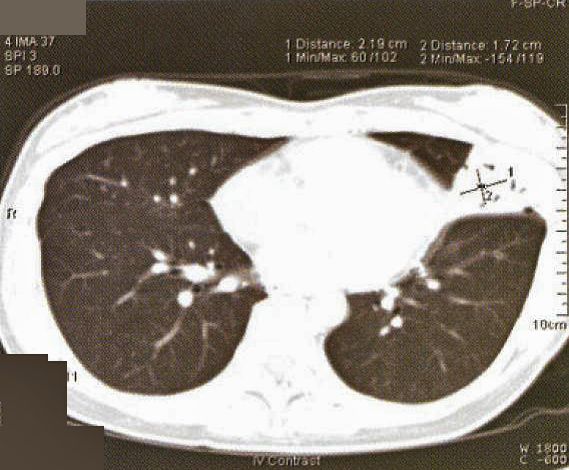

Fig. 1: CXR taken at presentation (a) and 17 days later (b). Left mid zone opacity remained unchanged despite a course of Azithromycin Blood tests revealed normal CBP, ESR & routine biochemistry. Antibodies for HIV 1 & 2 were negative. Thyroid function was normal but thyroid peroxidase antibody was elevated at 81.7 IV/ml (normal <12). CT thorax showed an area of segmental consolidation in the lingular segment of left upper lobe (fig. 2a), with no abnormality detected in other parts of the lungs, mediastinum or body structures. Bronchoscopy revealed nothing abnormal and bronchial washings grew alpha streptococcus but were negative for AFB smear, M tuberculosis DNA or malignant cells. She developed a cough after the bronchoscopy and responded to a course of levofloxacin.

Fig. 1: CXR taken at presentation (a) and 17 days later (b). Left mid zone opacity remained unchanged despite a course of Azithromycin Blood tests revealed normal CBP, ESR & routine biochemistry. Antibodies for HIV 1 & 2 were negative. Thyroid function was normal but thyroid peroxidase antibody was elevated at 81.7 IV/ml (normal <12). CT thorax showed an area of segmental consolidation in the lingular segment of left upper lobe (fig. 2a), with no abnormality detected in other parts of the lungs, mediastinum or body structures. Bronchoscopy revealed nothing abnormal and bronchial washings grew alpha streptococcus but were negative for AFB smear, M tuberculosis DNA or malignant cells. She developed a cough after the bronchoscopy and responded to a course of levofloxacin.

She was treated with chemotherapy – 3-weekly regime of cyclophosphamide, adriamycin, vincristine & prednisolone (CHOP) – and tolerated the treatment well. A CT thorax was performed after 3 cycles of chemotherapy showed a slight reduction in the area of consolidation (fig. 2b).

The radiographic changes of pulmonary MALToma are non-specific. CXR and High resolution CT thorax usually show multi-focal, ill-defined nodules containing air bronchograms or focal lobar consolidation similar to what is seen in this patient. Mediastinal lymphadenopathy and pleural changes are rare. These features are similar to those seen in bronchoalveolar cell carcinoma or bronchiolitis obliterans with organizing pneumonia (3). The possibility of MALToma should be considered in patients with non-resolving pneumonia, especially if there is an absence of prominent systemic or respiratory symptoms.